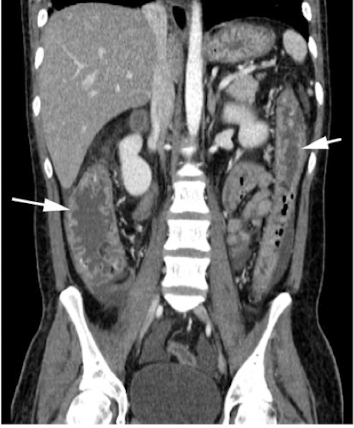

What is this and what type of scan

Polycystic kidney disease, CT scan